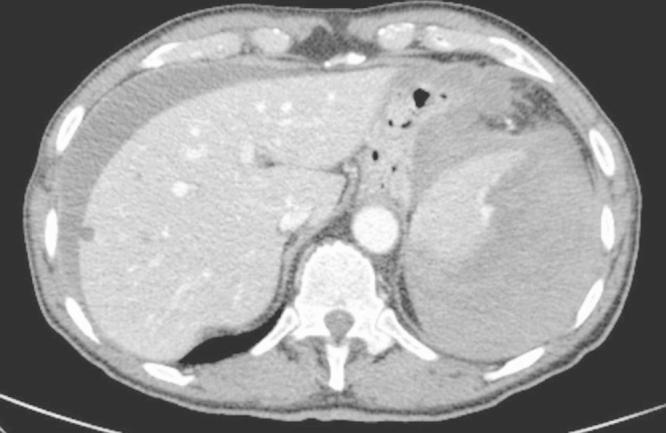

We report the case of a 73-year old man who presented to surgical consultation 50h after colonoscopy. Clinical, laboratory and imaging findings were suggestive for haemoperitoneum. At surgery an almost complete splenic disruption was evident and urgent splenectomy was performed.

我们报告一例73岁男性患者,在结肠镜检查后50小时前来外科会诊。临床、实验室和影像学检查结果提示存在腹腔积血。手术中可见脾脏几乎完全破裂,遂紧急行脾切除术。